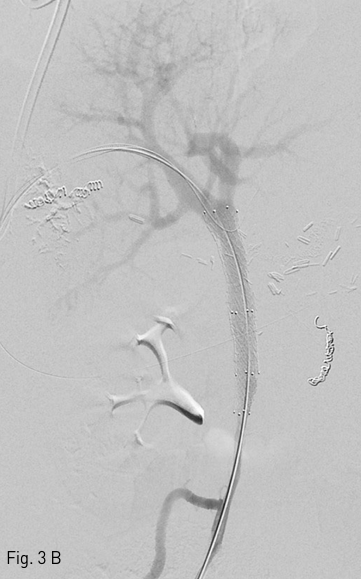

Fig 3A

(A) Guide wire via ileal vein which passes through obstructed lesion of portal vein was snared via percutaneous portal vein tract.